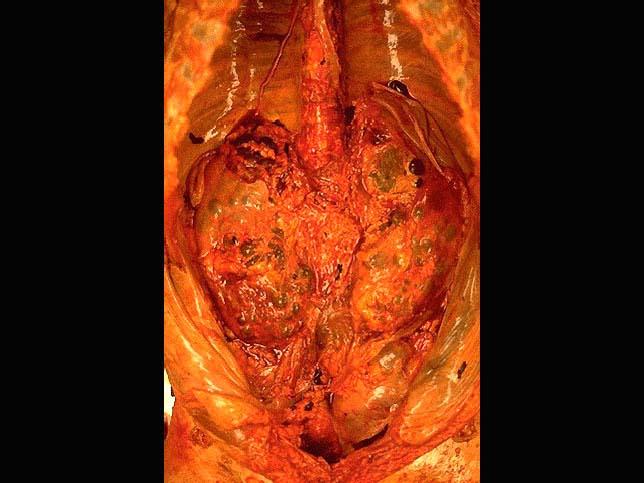

问题 成年男尸,尸检时发现其双侧肾脏肿大,由许多大小不一的囊腔构成,大体如图所示,镜下如图所示,请做出病理诊断 ( )

选项 A.肾细胞癌 B.多囊性肾病 C.肾结核 D.孤立性肾囊肿 E.肾脓肿

答案 B